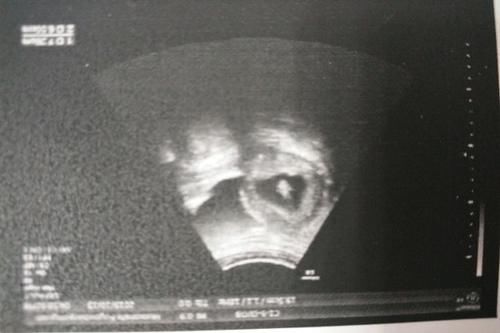

【B超次数太多,会影响到胎儿健康吗?关于B超,医生给你说清楚】我们都知道,孕妇怀孕的时间是十个月,也就是40周的时间。足月出生的宝宝都比早产的宝宝要健康许多。那么在第一次检查B超的时间是在怀孕12至16周之间。这个时间段腹中的胎儿已经基本成型了,所以此时做B超一方面是观察胎儿发育情况,还有就是能够较为精准的推测孕妇怀孕的天数,也能更好的判断预产期是在什么时候。第2次做B超是在怀孕20周至25周,这时的胎儿发育较快,所有的不确定性都会在此时出现。比如一些存在畸形的胎儿,都可以在这个时间段排查出来。所以第二次B超检查是非常重要的孕期检查。第三次B超检查是临近生产前的最后一次检查,医生可以通过观察胎儿的发育程度和一些脐带有无绕颈的情况,为分娩做最后的产前准备。